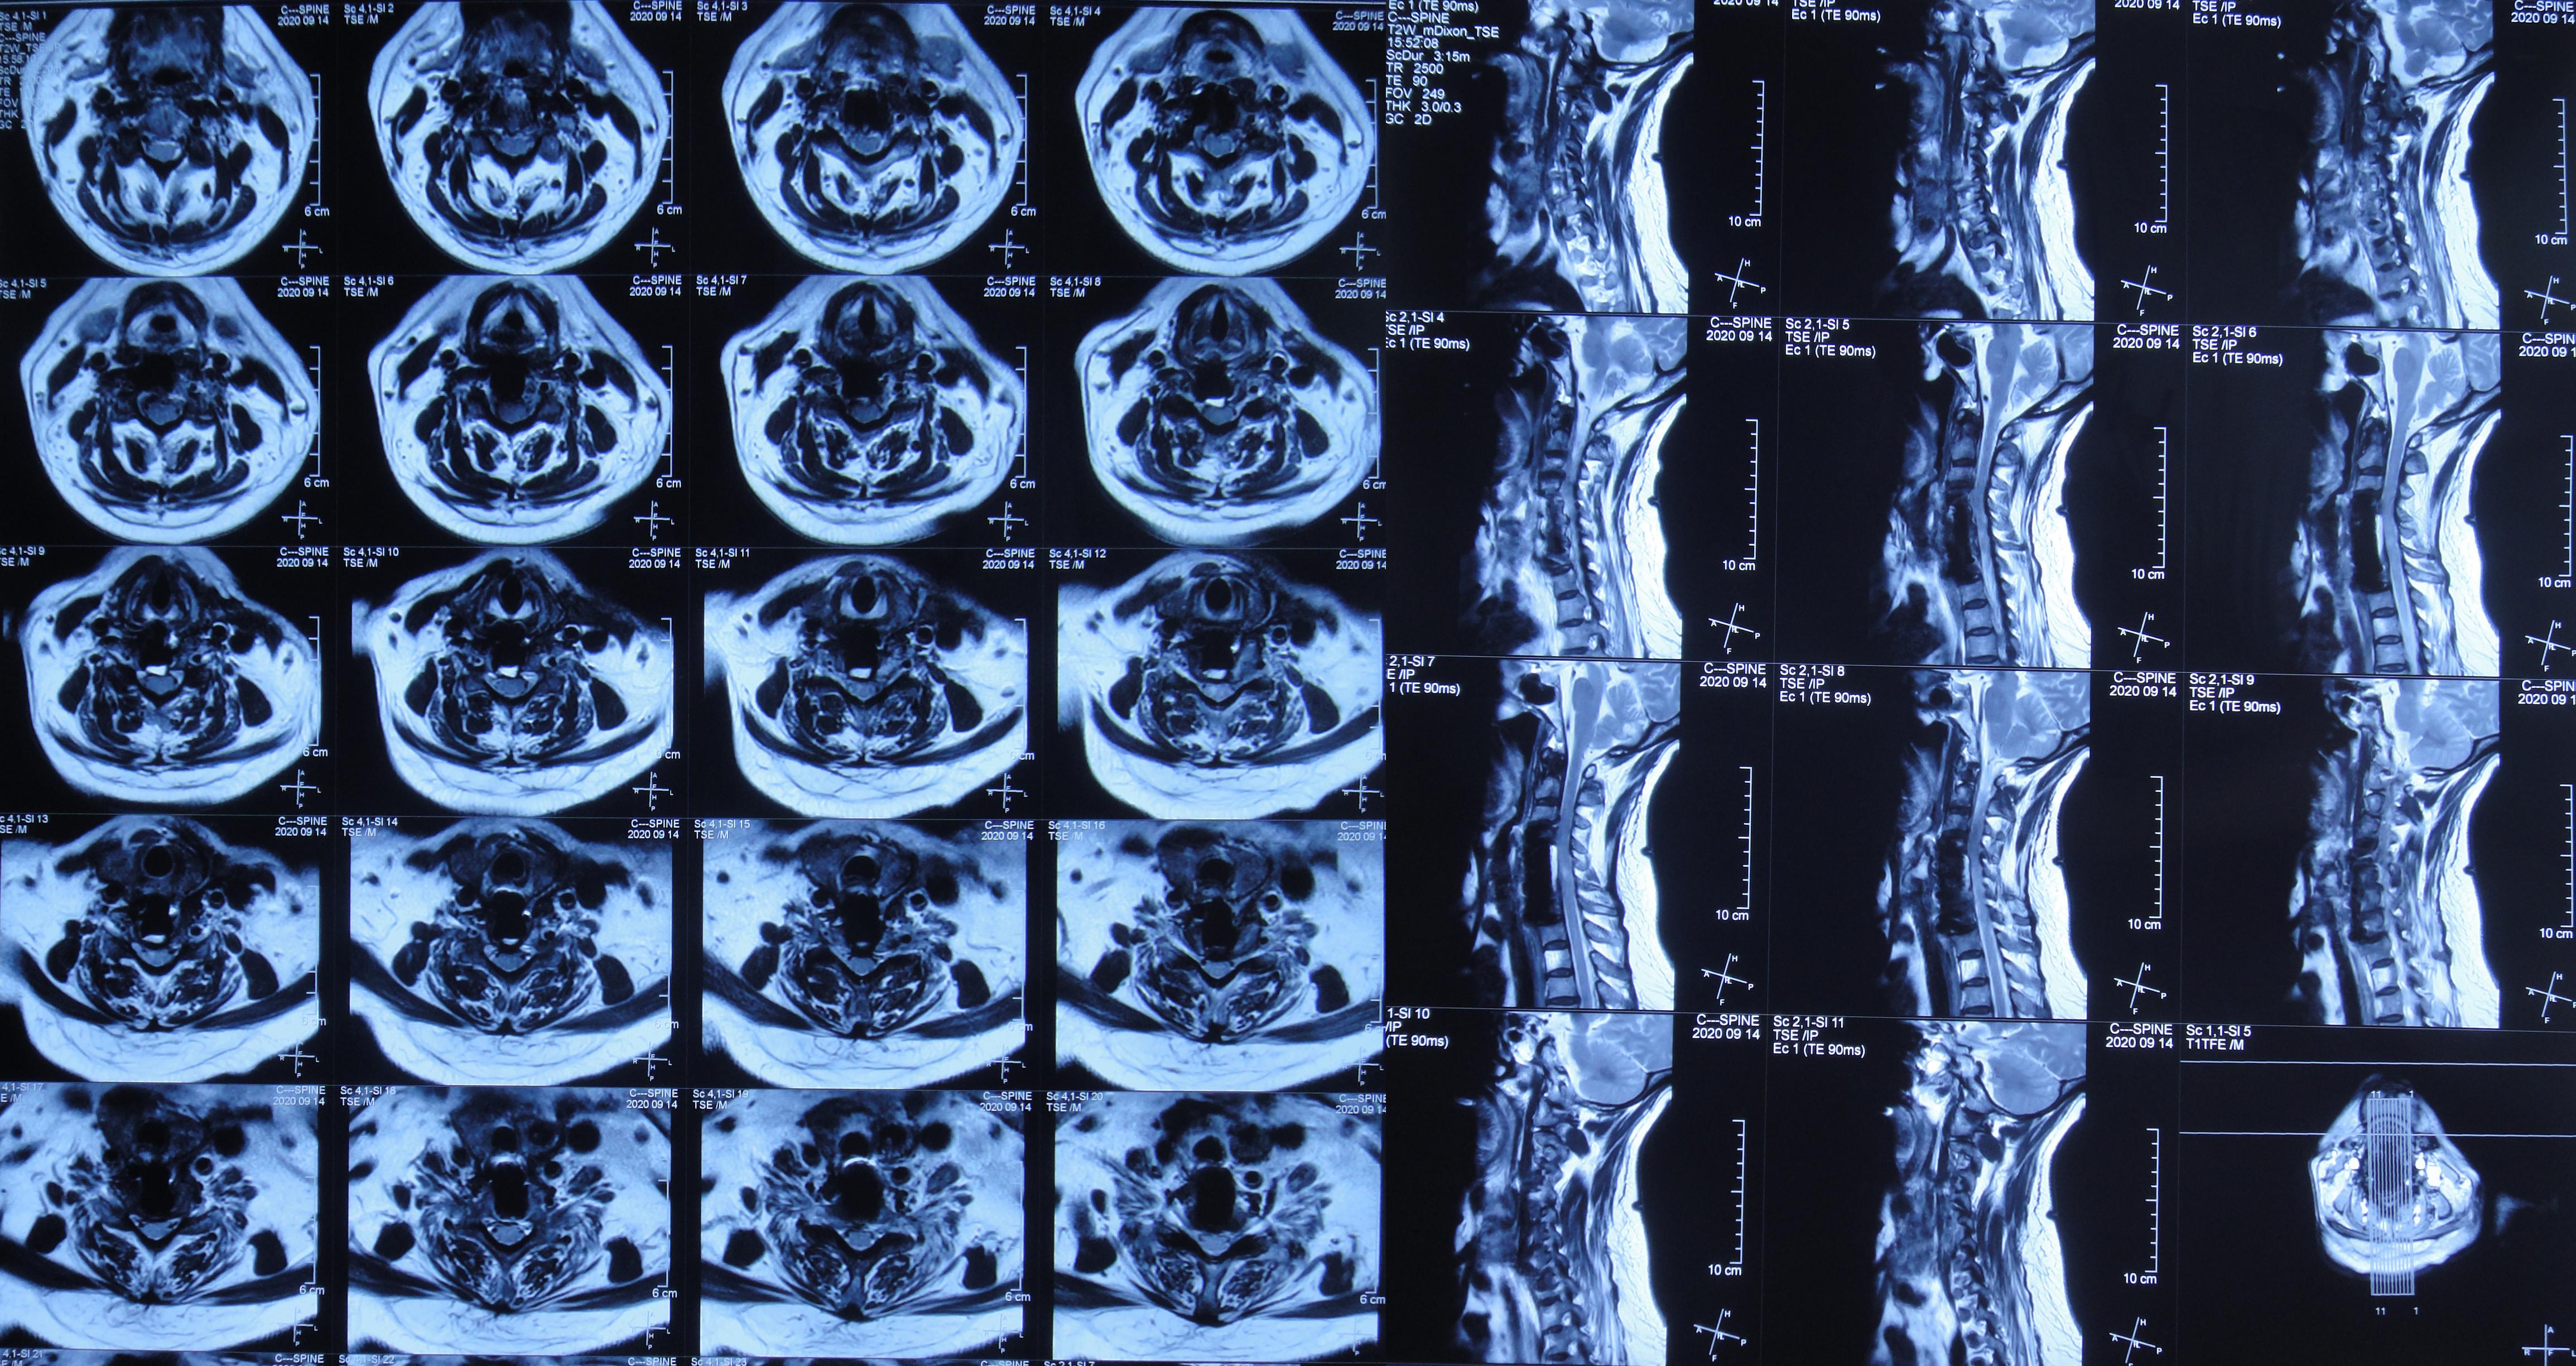

2020年9月2日(入脑脊液科次日,即颈椎脑脊液漏修补术后第6天,即第二次颈椎病术后第25天)复查颈部MR示术区皮下深部仍有包裹性积液( 图-10 )。

图-10: 2020年9月2日颈部MR

2020年9月14日(入脑脊液科第14天,即脑室外引流术后第11天,即颈椎脑脊液漏修补术后第18天,即第二次颈椎病术后第31天)复查颈部MR示皮下积液已基本消失( 图-13 )。

图-13: 2020年9月14日

2020年9月28日(入脑脊液科第28天,即脑室外引流术后第25天,即颈椎脑脊液漏修补术后第32天,即第二次颈椎病术后第45天)复查颈部MR:术区皮下积液消失( 图-16 ),于是当日拔除脑室引流管。

图-16: 2020年9月28日颈部MR